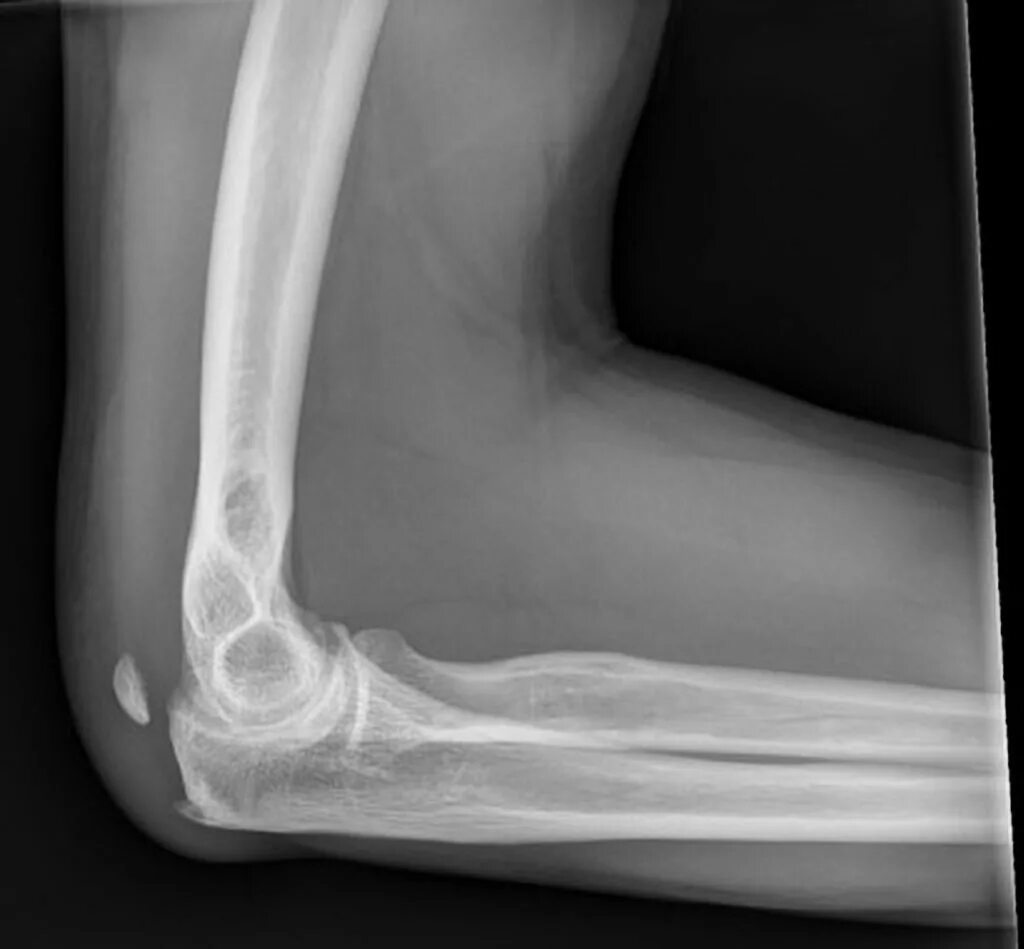

Обызвествление сухожилий мышц